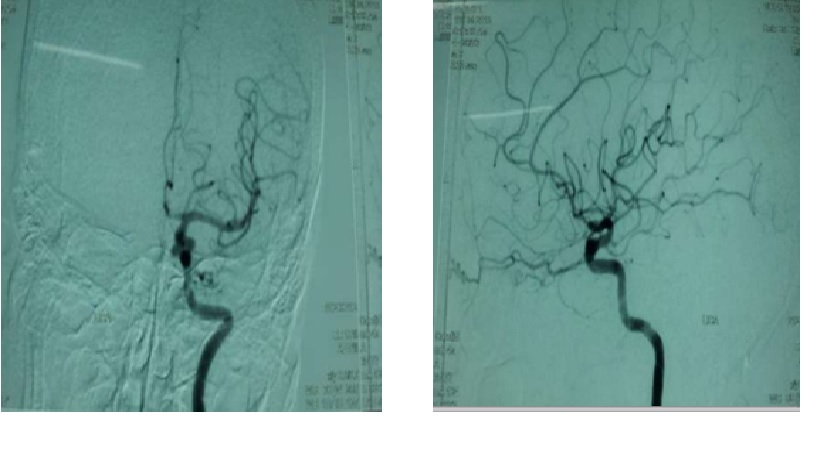

BN được chỉ định DSA

CTA

Chẩn đoán hình ảnh: 3 túi phình động mạch cảnh trong bên (P) đoạn quanh động mạch mắt.Túi phình 1:2.4x2mm,cổ 2.4mm.Túi phình 2:2.5×2.4mm,cổ 2.2mm.Túi phình 3:3.7x3mm,cổ 3mm. -2 túi phình động mạch cảnh trong bên (T) đoạn quanh động mạch mắt.Túi phĩnh 4:3.4×3.7 mm,cổ 3.4mm.Túi phình 5:3.7×4.3 mm,cổ 3.7 mm. -1 túi phình động mạch đỉnh thân nền : 4×3.7×4.3mm,cổ 3.7 mm.

Chẩn đoán xác định: Xuất huyết dưới nhện do vỡ đa túi phình mạch não

MRI não sẽ phát hiện các nguyên nhân khác có thể gây ra SAH như AVM và các khối u. Nó cũng đánh giá sự hiện diện của bất kỳ tổn thương nhu mô não nào (ví dụ, nhồi máu). Chụp mạch MRA và CT thường được sử dụng như một xét nghiệm sàng lọc để phát hiện chứng phình động mạch lớn. Tiêu chuẩn vàng là thực hiện chụp động mạch cảnh và động mạch đốt sống (độ nhạy ∼85%). Hạn chế là thủ thuật xâm lấn.

Chụp mạch máu não (CT angiography (CTA), Digital subtraction angiography (DSA)

Chụp mạch máu não là bước tiếp theo đối với tất cả bệnh nhân chẩn đoán CT, chọc dò thắt lưng, hoặc MRI. Tiêu chuẩn vàng của hình ảnh mạch máu vẫn là DSA. Chụp CT mạch máu (CTA) trở nên phổ biến và hiện thường được thực hiện đầu tiên chụp mạch máu ở nhiều cơ sở. Tùy thuộc vào kỹ thuật, độ dày lát cắt, độ nhạy và độ đặc hiệu của CTA có thể dao động lần lượt từ 90% đến 97% và 93% đến 100% khi so sánh đến DSA. Tuy nhiên, CTA có thể bỏ sót các túi phình nhỏ từ 4 mm trở xuống.